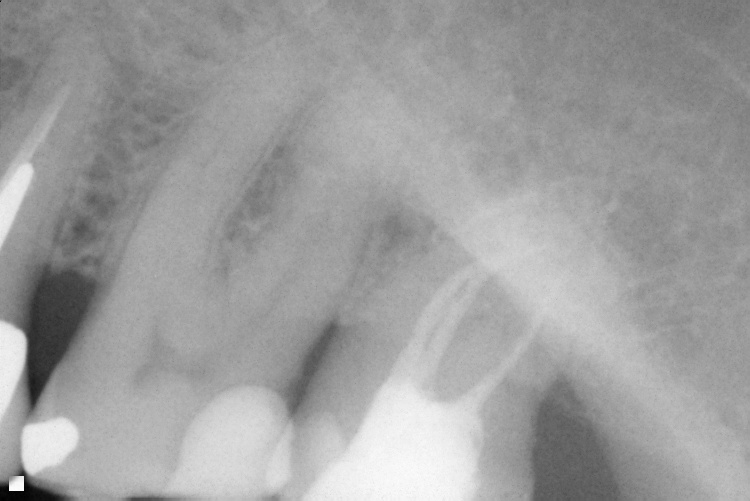

Name Last modified Size Description Parent Directory - IO000001.jpg 2020-07-28 13:36 71K IO000002.jpg 2020-07-28 13:36 88K IO000003.jpg 2020-07-28 13:36 82K IO000004.jpg 2020-07-28 13:36 85K